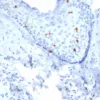

Formalin-fixed, paraffin-embedded human skin stained with Langerin Mouse Monoclonal Antibody (LGRN/7430). HIER: Tris/EDTA, pH9.0, 45min. 2°C: HRP-polymer, 30min. DAB, 5min.

Langerhans cells (LCs) are a subset of immature dendritic cells (DCs) that specifically localize in the epidermis and other mucosal epithelia. Epidermal LCs possess strong immuno-stimulatory capacity and play a central role in the initiation and regulation of immune responses. Langerin (CD207) is a Ca2+-dependent, C-type lectin domain containing, type II transmembrane protein that induces epidermal LCs to differentiate into Birbeck granules (BG). BGs are organelles with superimposing and zippering membranes that influence proper class I type antigen presentation to the circulating T cells. Human spleen, lymph node, thymus, liver, lung and heart express Langerin protein.